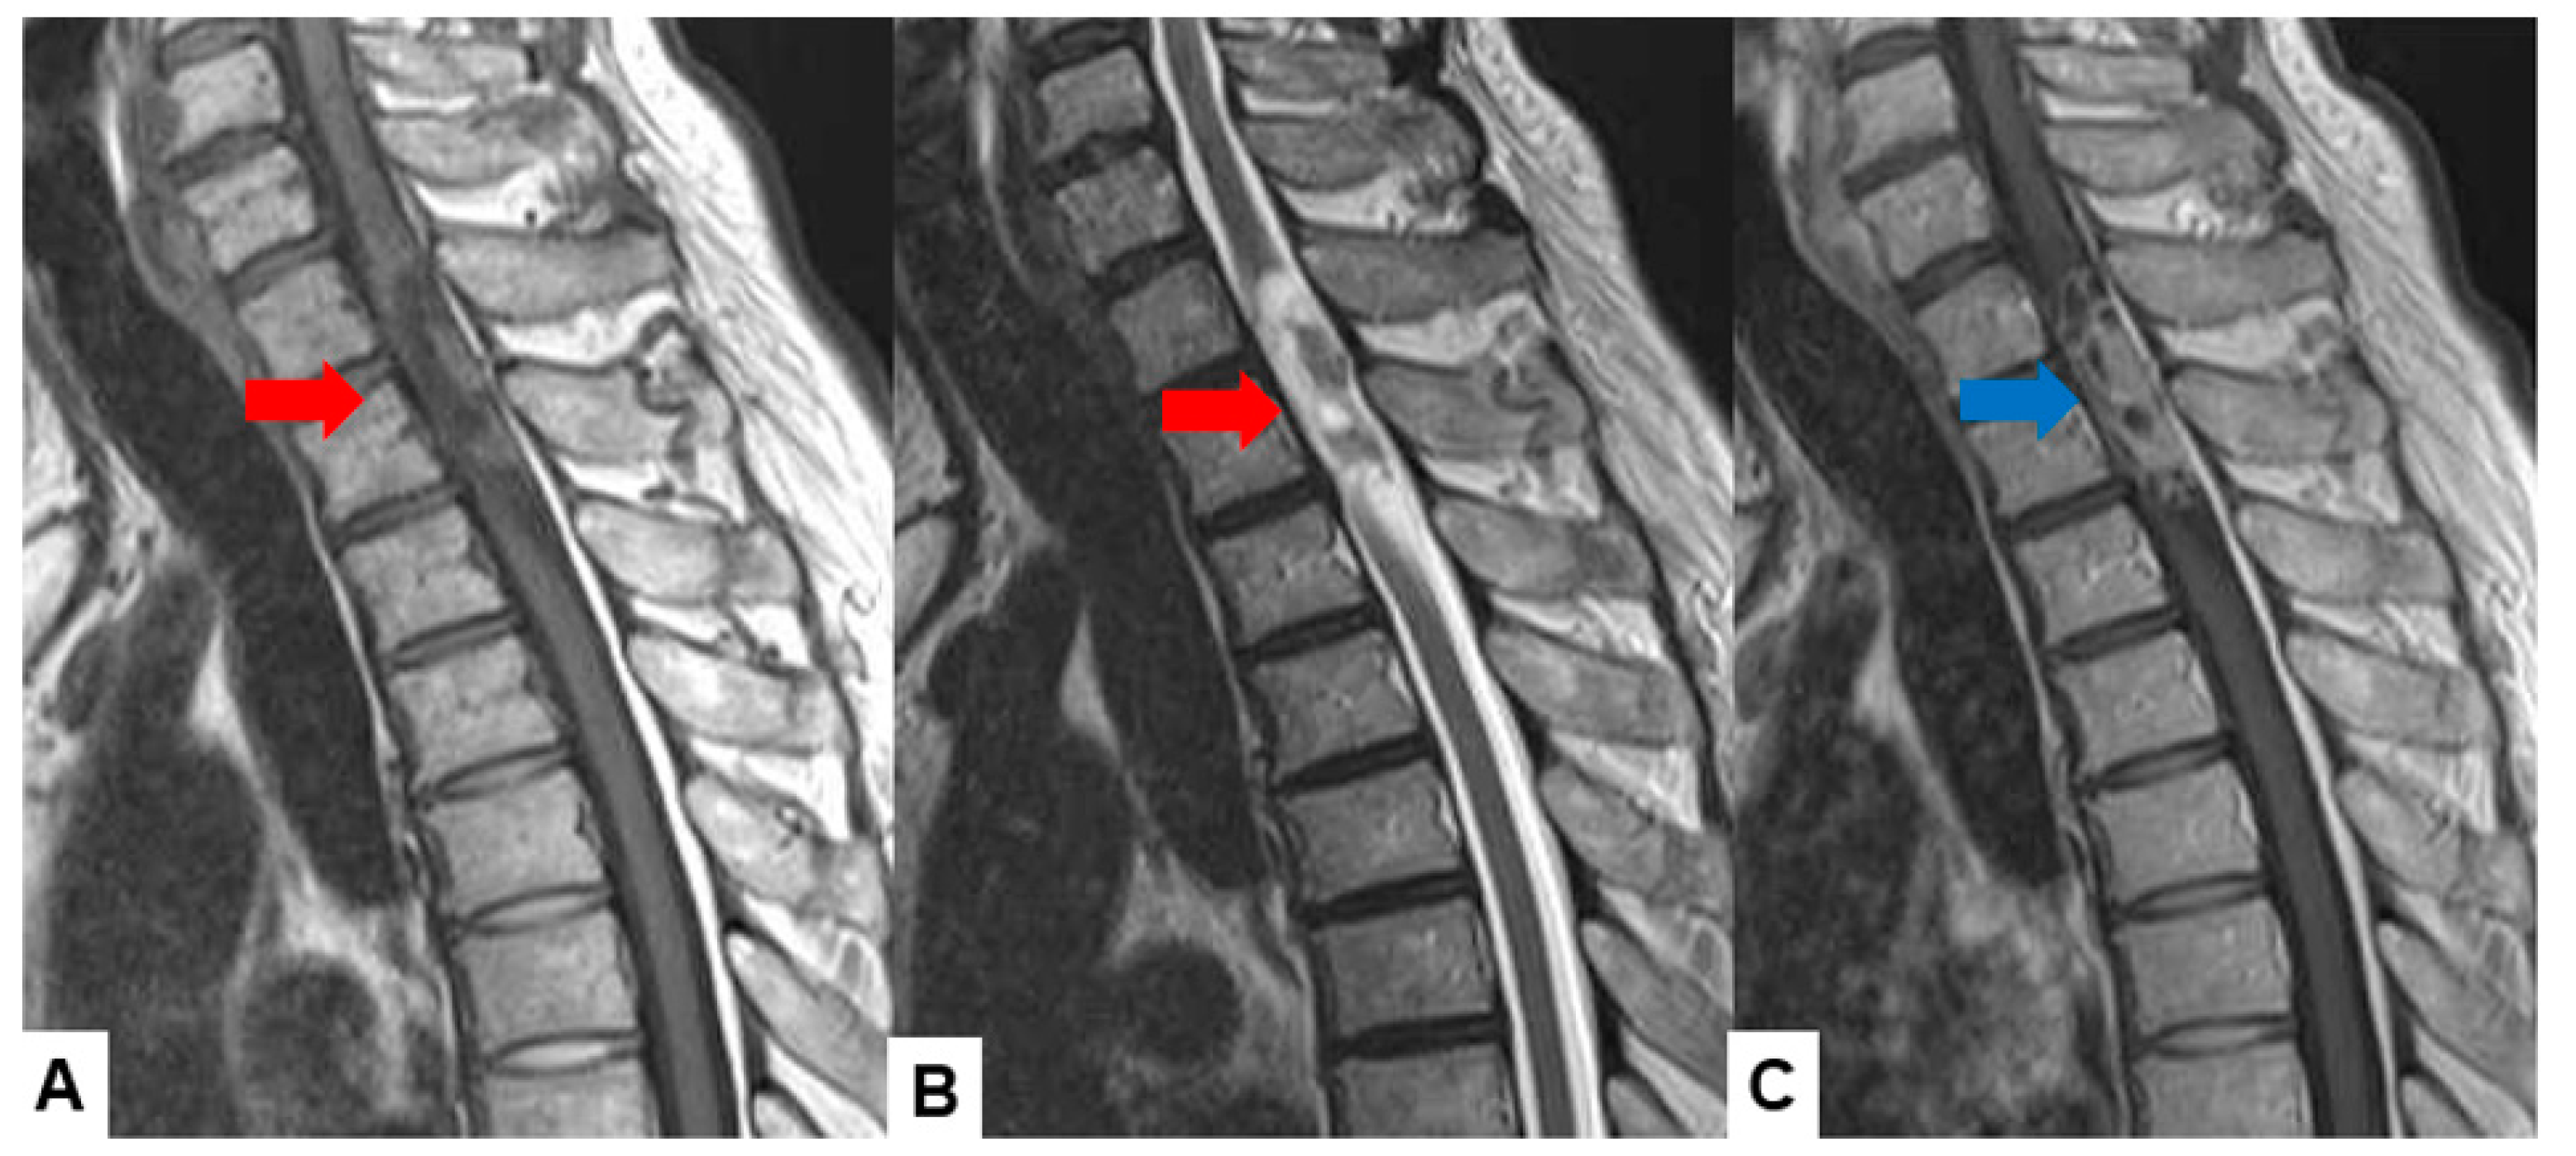

2.1. MRI and CT